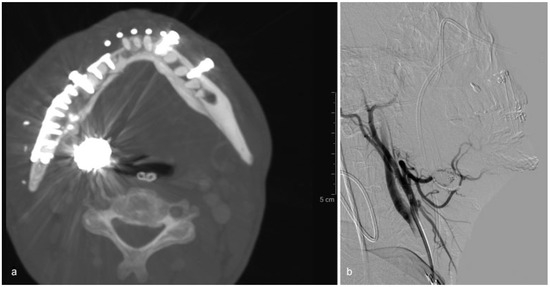

To clarify the conflicting recommendations for care of blowout fracture (BOF), a prospective randomized study is required. Here, we present a prospective randomized pilot study on BOF. This article aimed to evaluate which computed tomography (CT) fin...